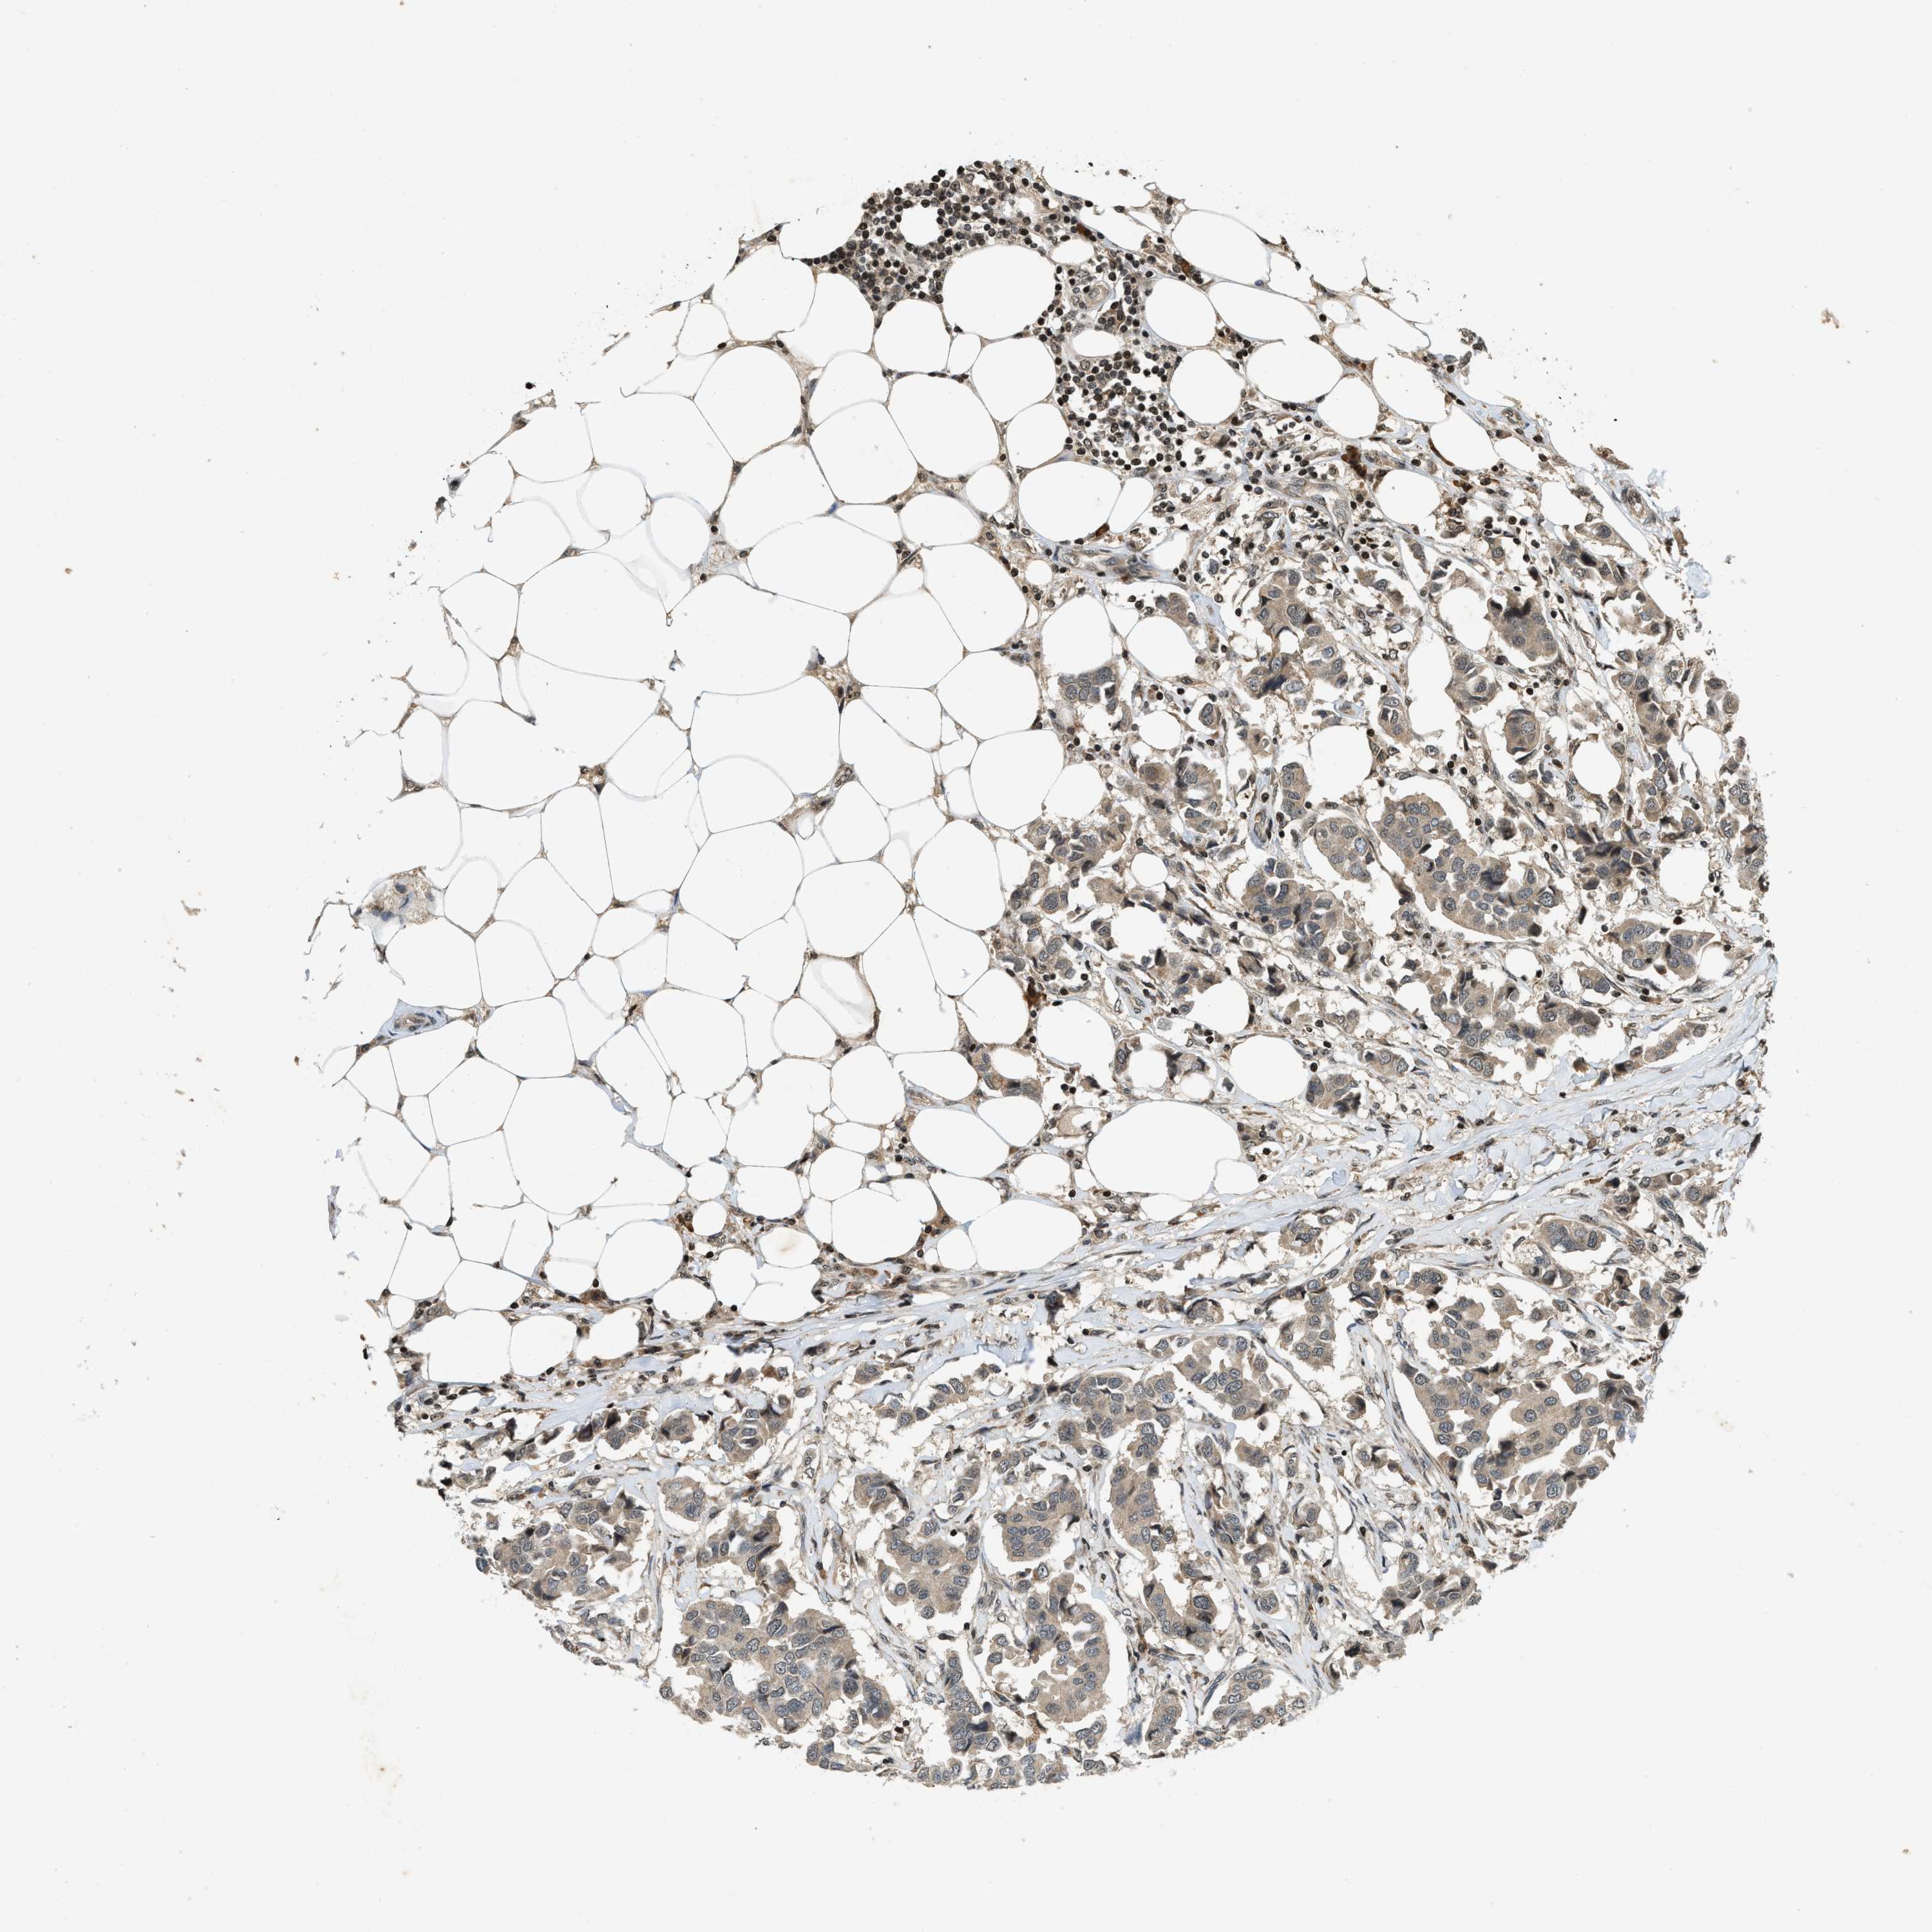

SIAH1

CANCER BREAST CANCER Show tissue menu

Breast cancer

Human cancer